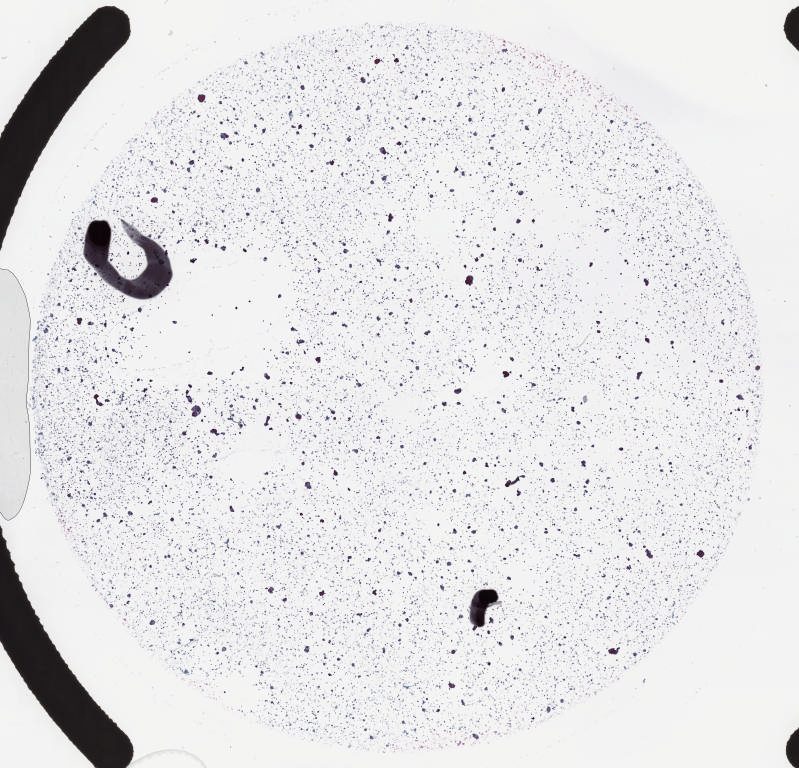

Case8 pax8.svs

101592

x

39406

@

40X